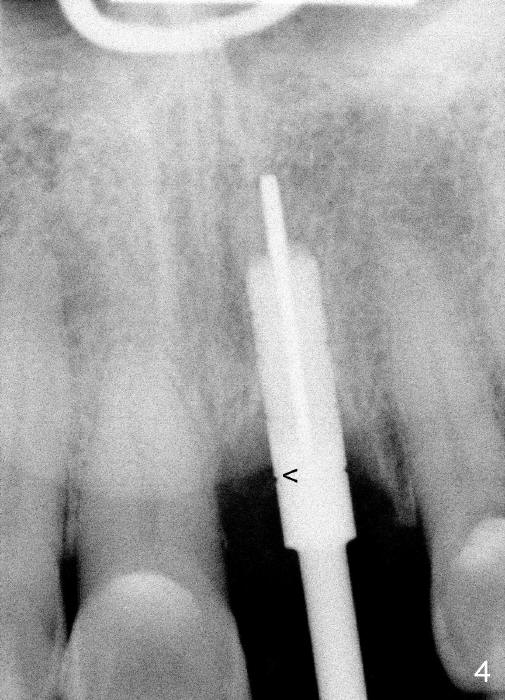

After extraction, osteotomy is made as palatally as possible so that the end of a reamer/drill (Fig.3 R) in the line of the incisal edge of the neighboring teeth. The depth of the 3.5 mm reamer is 14 mm from the crest (Fig.4 <). Next, a 5x17 mm tapered implant is placed with insertion torque > 60 Ncm (Fig.6). A 4 mm 0° unipost is permanently cemented (Fig.5: P). Finally a provisional is cemented on a temporary basis (Fig.7,8: T). There is no contact in centric or any lateral excursions.